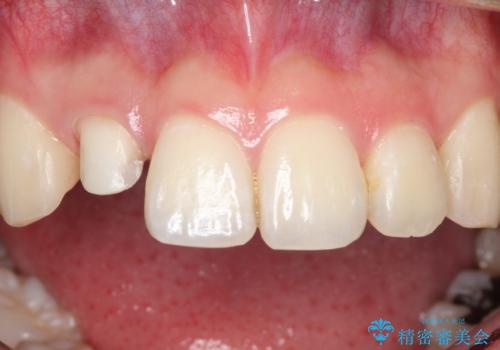

根管治療を含め、オールセラミッククラウンにて修復治療を行っております。

今回は歯冠修復にe-maxプレスクラウンを使っています。